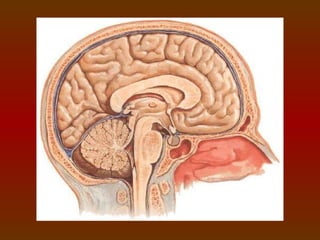

Tanto o encéfalo quanto à medula espinhal são envolvidos por três

envoltórios ou membranas protetoras denominadas meninges.

DURA-MÁTER

 A mais externa e significa “mãe dura”. Camada forte e fibrosa que

possui uma camada interna (juntam-se para formar a foice

cerebral) e outra externa (adere-se à camada interna da calota

craniana).

PIA-MÁTER

 A mais interna e significa “mãe delicada”. Muito fina e

vascularizada, repousa junto ao cérebro (envolvendo-o

totalmente) e a medula espinhal.

ARACNÓIDE

 Localizada entre a pia-máter e a dura-máter e significa . Sinonímia

Aracnídea.